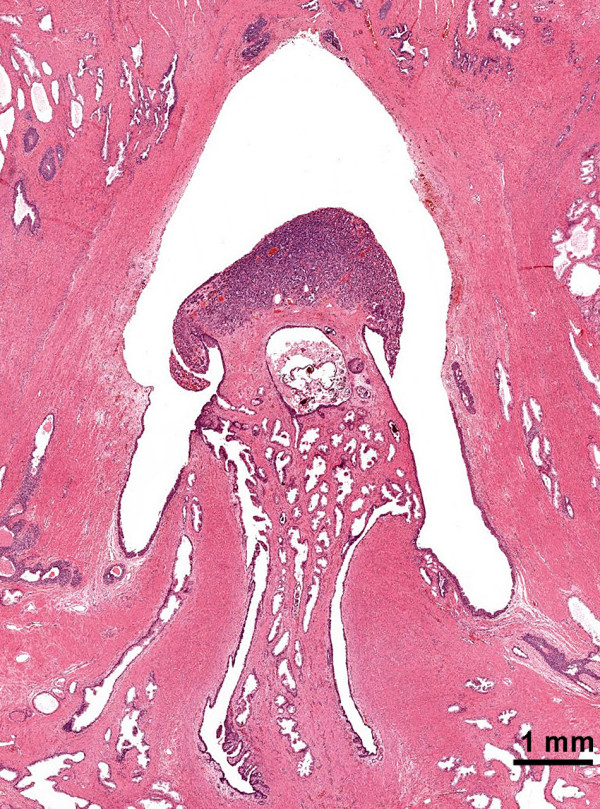

患者尿道前列腺部的精阜内部距侵袭性腺癌约17 mm处,有一个最大尺寸为3 mm、形态学与腺癌显著不同的肿瘤。该肿瘤在低倍显微镜下看起来边界清楚,边缘推挤,无浸润(图 3)。高倍显微镜观察发现细胞形成巢状、腺泡和小梁结构,细胞核小,大小一致,染色质呈颗粒状“盐和胡椒”形态,有中等量的颗粒状胞浆(图 2A)。未见细胞有丝分裂相、坏死以及侵袭血管淋巴系统。尿道肿瘤细胞的嗜铬粒蛋白A、神经元特异性烯醇化酶和突触素的免疫过氧化物酶染色几乎100%为阳性,在胞浆中呈颗粒状分布(图 4)。这些细胞的广谱细胞角蛋白和PSA是阴性的。前列腺腺癌细胞的PSA免疫过氧化物酶染色阳性,消旋酶[α-甲基 CoA]抗原染色亦为阳性,p63抗原染色为阴性。根据这种反应模式,我们得出结论:这两种肿瘤是不同的,将患者尿道的肿瘤诊断为类癌。我们试图用电镜观察患者尿道肿瘤有无神经分泌颗粒,但是因福尔马林固定有伪影而没有成功。

图 3。尿道前列腺部的精阜类癌,苏木精-伊红染色(2×物镜)。